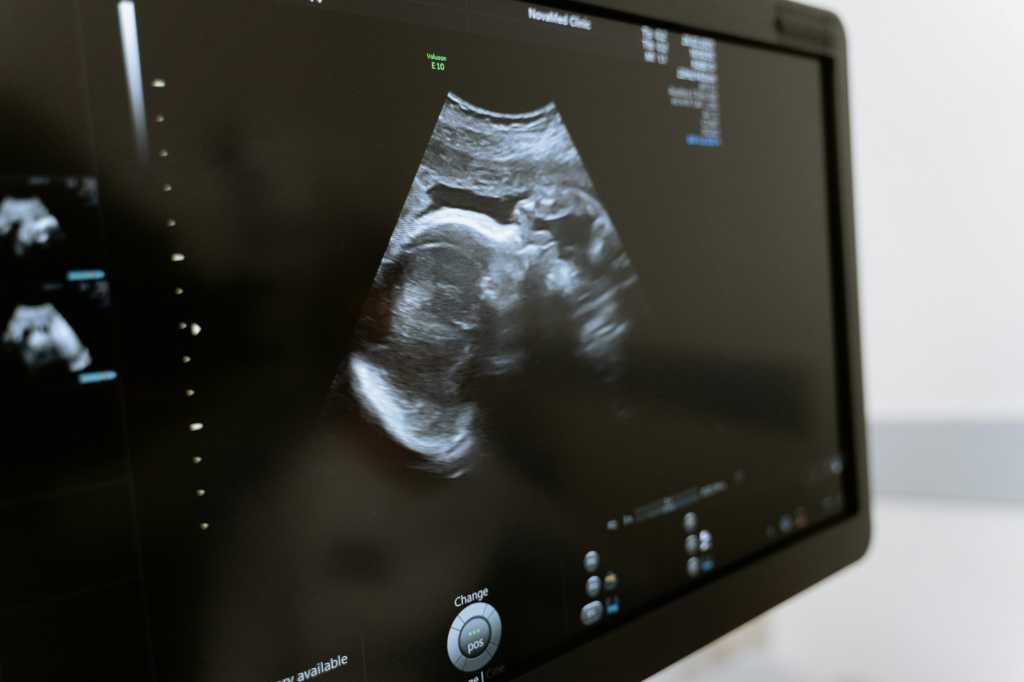

Siden 1. december sidste år har borgere i Region Hovedstaden kunnet få gratis fertilitetsbehandling til barn nummer to. Den nye ordning giver ret til op til tre behandlinger med IVF eller ICSI på statens regning.

Regionens offentlige fertilitetsklinikker har oplevet en betydelig stigning i behandlingsaktiviteten, med cirka 30-50 procent flere behandlinger sammenlignet med samme periode året før.

Fra december til april modtog klinikkerne omkring 1110 henvisninger til fertilitetsbehandling målrettet andet barn. Det vidner om en øget efterspørgsel og større adgang til fertilitetsbehandling for familier, der ønsker flere børn.